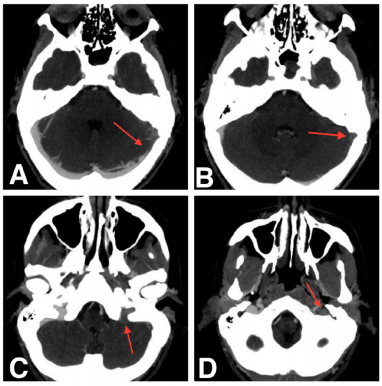

The patient returned to the emergency department with complaints of a sudden strong left parieto-temporal headache, confusion and blurred vision 25 days after the traumatic event. A cranial CT scan showed complete resolution of the SDH and pneumocephaly (Figure 3). Even though the intracranial lesions had had a natural evolution, the patient was still symptomatic and now presented with an altered state of consciousness (GCS 13 - E3M6V4). Thus, a CT venogram was performed, which identified an absence of contrast enhancement on the left distal third of transverse (Figure 4A) and sigmoid (Figure 4B) sinus and on the left internal jugular vein, compatible with DST (Figure 4C & 4D). The patient immediately started anticoagulation therapy with enoxaparin 80 mg twice a day for 4 days and warfarin for 1 year. Recently, at the 14-month follow-up, a complete dissolution of the thrombus and dural sinus recanalization were identified in the CT venogram. Genetic or acquired thrombophilia, vasculitis, and neoplastic disease were excluded.

Figure 4A Thrombosis of the left distal third of Transverse Sinus.

Figure 4B Thrombosis of the left Sigmoid Sinus.

Figure 4C Thrombosis of the left Internal Jugular Vein before the jugular foramen.

Figure 4D Thrombosis of the left Internal Jugular Vein after the jugular foramen.